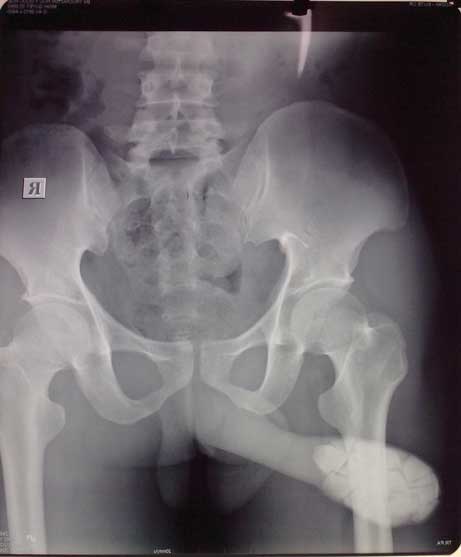

Hình 2: X quang cho thấy sỏi ở trong bao quy đầu